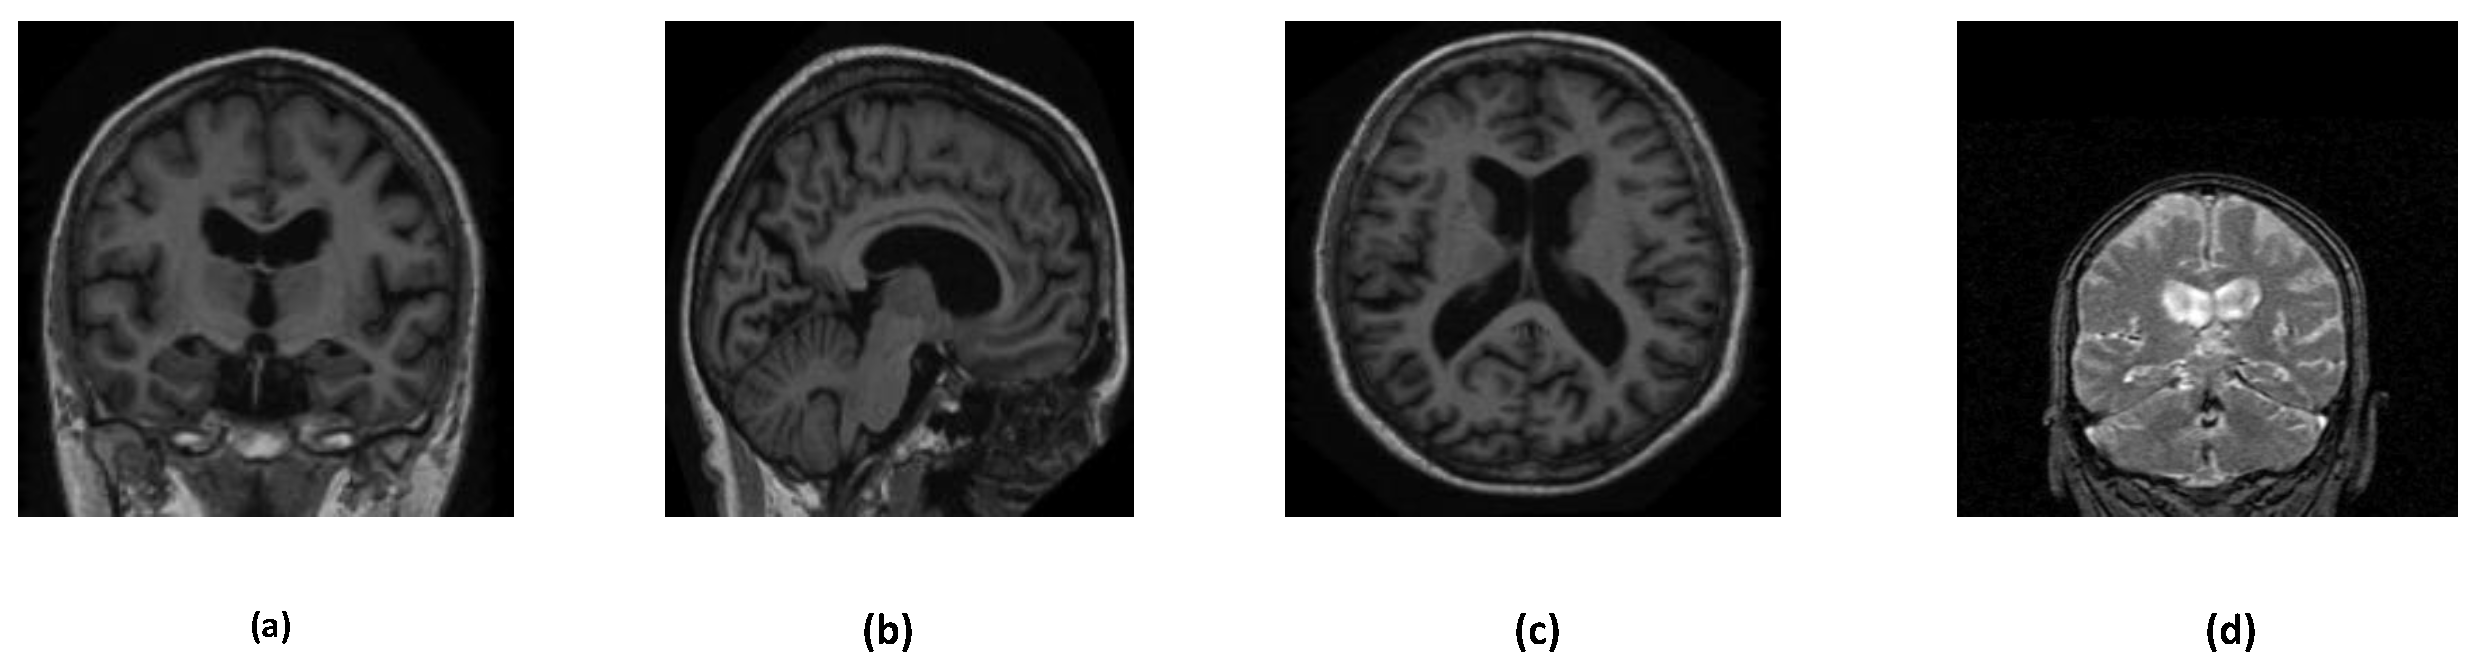

Alzheimer’s disease can be detected in many ways, such as, brain MRI, PET scan images, neurological evaluations, and so on. In this study, we have used two different brain MRI images dataset: ADNI and OASIS. Further, these datasets are divided into many subsets including augmented sets, merged sets etc. Figure 3 describes the overall structure of the datasets. Various orientations of MRI images are depicted in Figure 2.

Figure 2. Different orientations of the OASIS and ADNI dataset MRI images. (a) Coronal Plane (OASIS dataset) (b) Sagittal Plane (OASIS dataset) (c) Transverse Plane (OASIS dataset) (d) Coronal Plane (ADNI dataset).